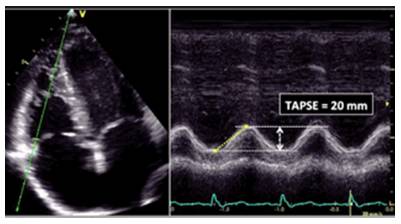

RV纵向收缩功能:

TAPSE(三尖瓣环收缩位移)